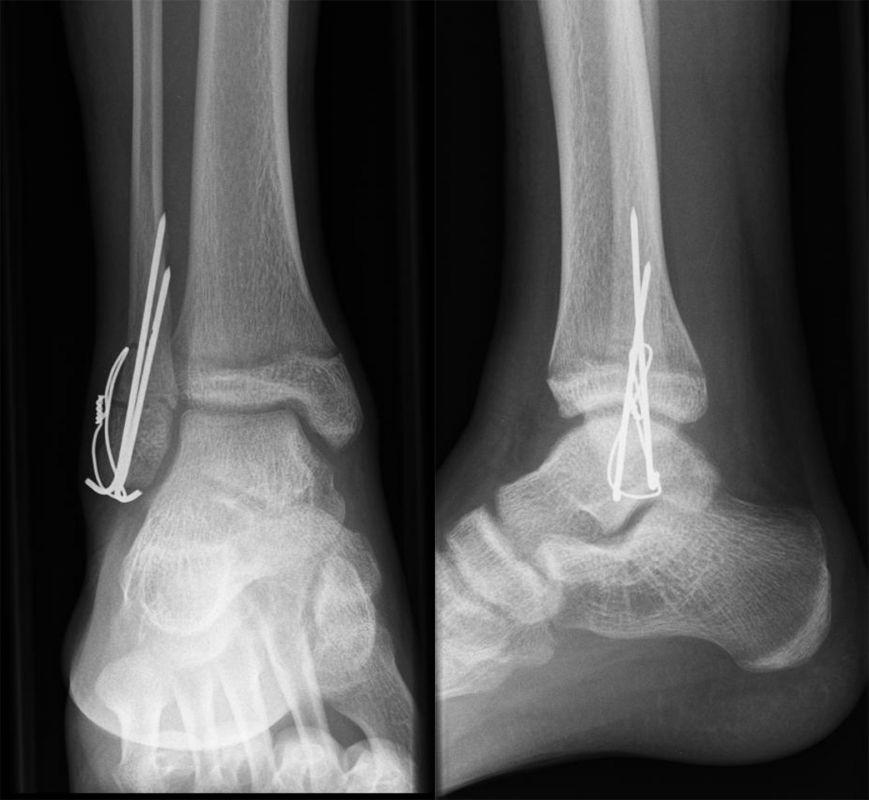

Behandlungsziel ist die exakte Rekonstruktion der Gelenkfläche sowie die Minimierung des Risikos einer späteren Wachstumsstörung. Dislozierte Frakturen werden offen reponiert, die Osteosynthese erfolgt mit einer Kleinfragmentschraube. Finden sich viele kleine Fragmente kann eine K-Draht Osteosynthese durchgeführt werden. Wird der Innenknöchel operiert, kann bei gleichzeitiger hochgradiger lateraler Instabilität eine Rekonstruktion des lateralen Bandapparats durchgeführt werden. Fibula Frakturen stellen sich meist spontan ein, sodass hier keine zusätzliche Osteosynthese notwendig ist.

Nach der Osteosynthese wird die Fraktur für ca. vier Wochen in einem Unterschenkelgips ruhiggestellt. Bei Schmerzfreiheit der Frakturzone erfolgt anschließend eine schmerzadaptierte Belastungssteigerung über weitere zwei Wochen. Sobald unter Alltagsbedingungen Beschwerdefreiheit besteht kann die sportliche Belastung langsam gesteigert werden. Kirschnerdrähte werden 6-8 Wochen postoperativ, Schrauben nach zwölf Wochen entfernt. Es empfiehlt sich klinische und radiologische Kontrollen im Abstand von 6 Monaten bis zum Wachstumsabschluss durchzuführen, um ein mögliches Fehlwachstum frühzeitig zu erkennen.